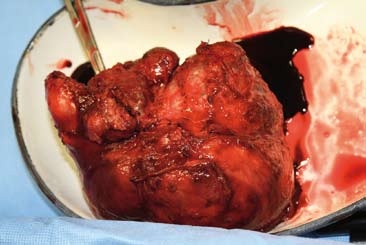

Transplantace jater má tři fáze - odběr orgánu od dárce, odstranění nemocných jater příjemce (hepatektomie) a transplantace dárcovských jater. Vlastní operaci předchází podrobné vyšetření potenciálního dárce. Jaterní štěp se většinou získává z mrtvého dárce, kadavera. Dárcovský orgán se musí před implantací příjemci upravit, to se nazývá „back table" a zahrnuje např. revizi žlučovodu či očištění žilních přítoků od zbytků bránice. Tato důležitá fáze transplantace probíhá před přenesením jater do těla příjemce. (5)

Při tomto zákroku jsou nejprve z těla příjemce odstraněna játra - hepatektomie, což je považováno za chirurgicky nejnáročnější část transplantace. Při samotné transplantaci se užívá techniky piggy-back, kdy se žíly jater našívají jako „batůžek" na dolní dutou žílu, poté je provedena anastomóza arteria hepatica a naposledy anastomóza žlučovodů, většinou koncem ke konci (tzv. end-to-end). Po celou dobu výkonu a především v jeho preanhepatické fázi je nemocný ohrožen velkou krevní ztrátou v důsledku koagulopatie doprovázející většinu jaterních onemocnění. (1, 6) Výkon je prováděn v celkové doplňované anestezii. Standardně se k operaci objednává z transfuzní stanice 7-10 TU resuspendovaných erytrocytů, 25 TU mražené plazmy (což není počet maximální, ale ani minimální) a v některých případech též trombocytový koncentrát. (1)

fota: Mgr. Jiří Čáp